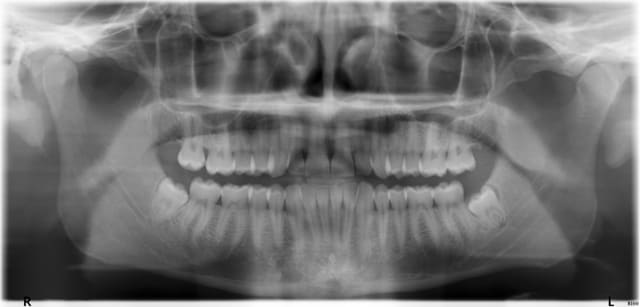

Je recherche les coordonnés d'un stomato pour prononcer un divorce entre un jeune patient très sympa ayant déménagé sur Paris 8ème et ses sagesse du bas.

Peut-être un scan ou cone beam à prévoir avant pour 38 (cf pano)